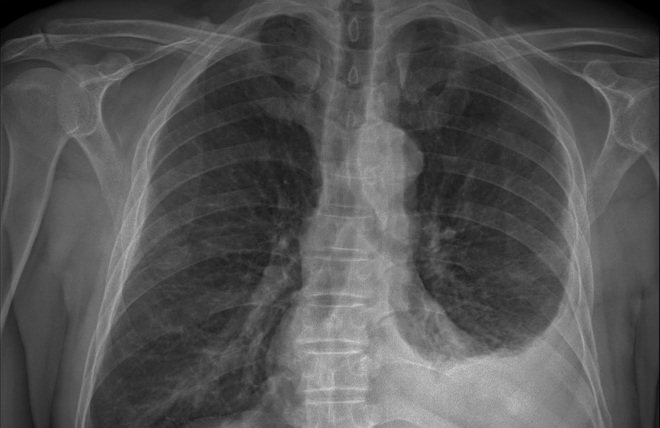

Рентген легких с описанием врача

Врач-рентгенолог при описании снимка легких анализирует следующие особенности:

- изображение сердца, которое слабо пропускает лучи, отображается тенью в центральной части;

- просветления легких с обеих сторон вместе с сосудистым рисунком и корнями (тяжистые линии);

- за сердцем и легкими прослеживается тень позвоночника, по которой можно оценить нормальное его положение или наличие искривления в боковой плоскости.

Проанализировав данные, сделаем вывод, что тень на классической обзорной рентгенограмме легких имеет белый цвет, а просветление – черный.

Элементы рентгенограммы, свидетельствующие о патологии легких:

- Кальцинированные тени (очаги с отложением кальция) – при туберкулезе.

- Множественные затемнения – опухоли и пневмония.

- Усиление легочного рисунка – при бронхите.

- Повышение прозрачности – при эмфиземе.

- Плевральное затемнение с косым верхним уровнем – плеврит (воспаление плевры).

- Расширение тени сердца – кардиомиопатия, сердечная недостаточность.

- Усиленное затемнение по контуру перикарда (внешняя оболочка сердца) – перикардит, «панцирное сердце».

Рентген легких назначается врачами чаще всего с целью исключения пневмонии. По косвенным признакам на снимке можно обнаружить и другие болезни:

- гидро- и пневмоторакс (скопление жидкости или воздуха в плевральной полости);

- хронический бронхит;

- туберкулез;

- бронхоэктатическая болезнь;

- профессиональные заболевания (силикозы, талькозы, асбестозы).

Курильщиков рентген выявляет по косвенным признакам: усиление и деформация легочного рисунка, скопление в корнях кальцинатов.

Косвенные признаки заболевания на снимке отнюдь не означают наличие патологии. Для установки диагноза необходим комплексный анализ результатов клинико-диагностических методов исследований.

Вследствие этого рентген органов грудной клетки выполняется после проведения других обследований. Такой подход также применяется в целях радиационной безопасности пациента, ведь иногда получение результатов других методов исследований исключает необходимость рентгеновского обследования.